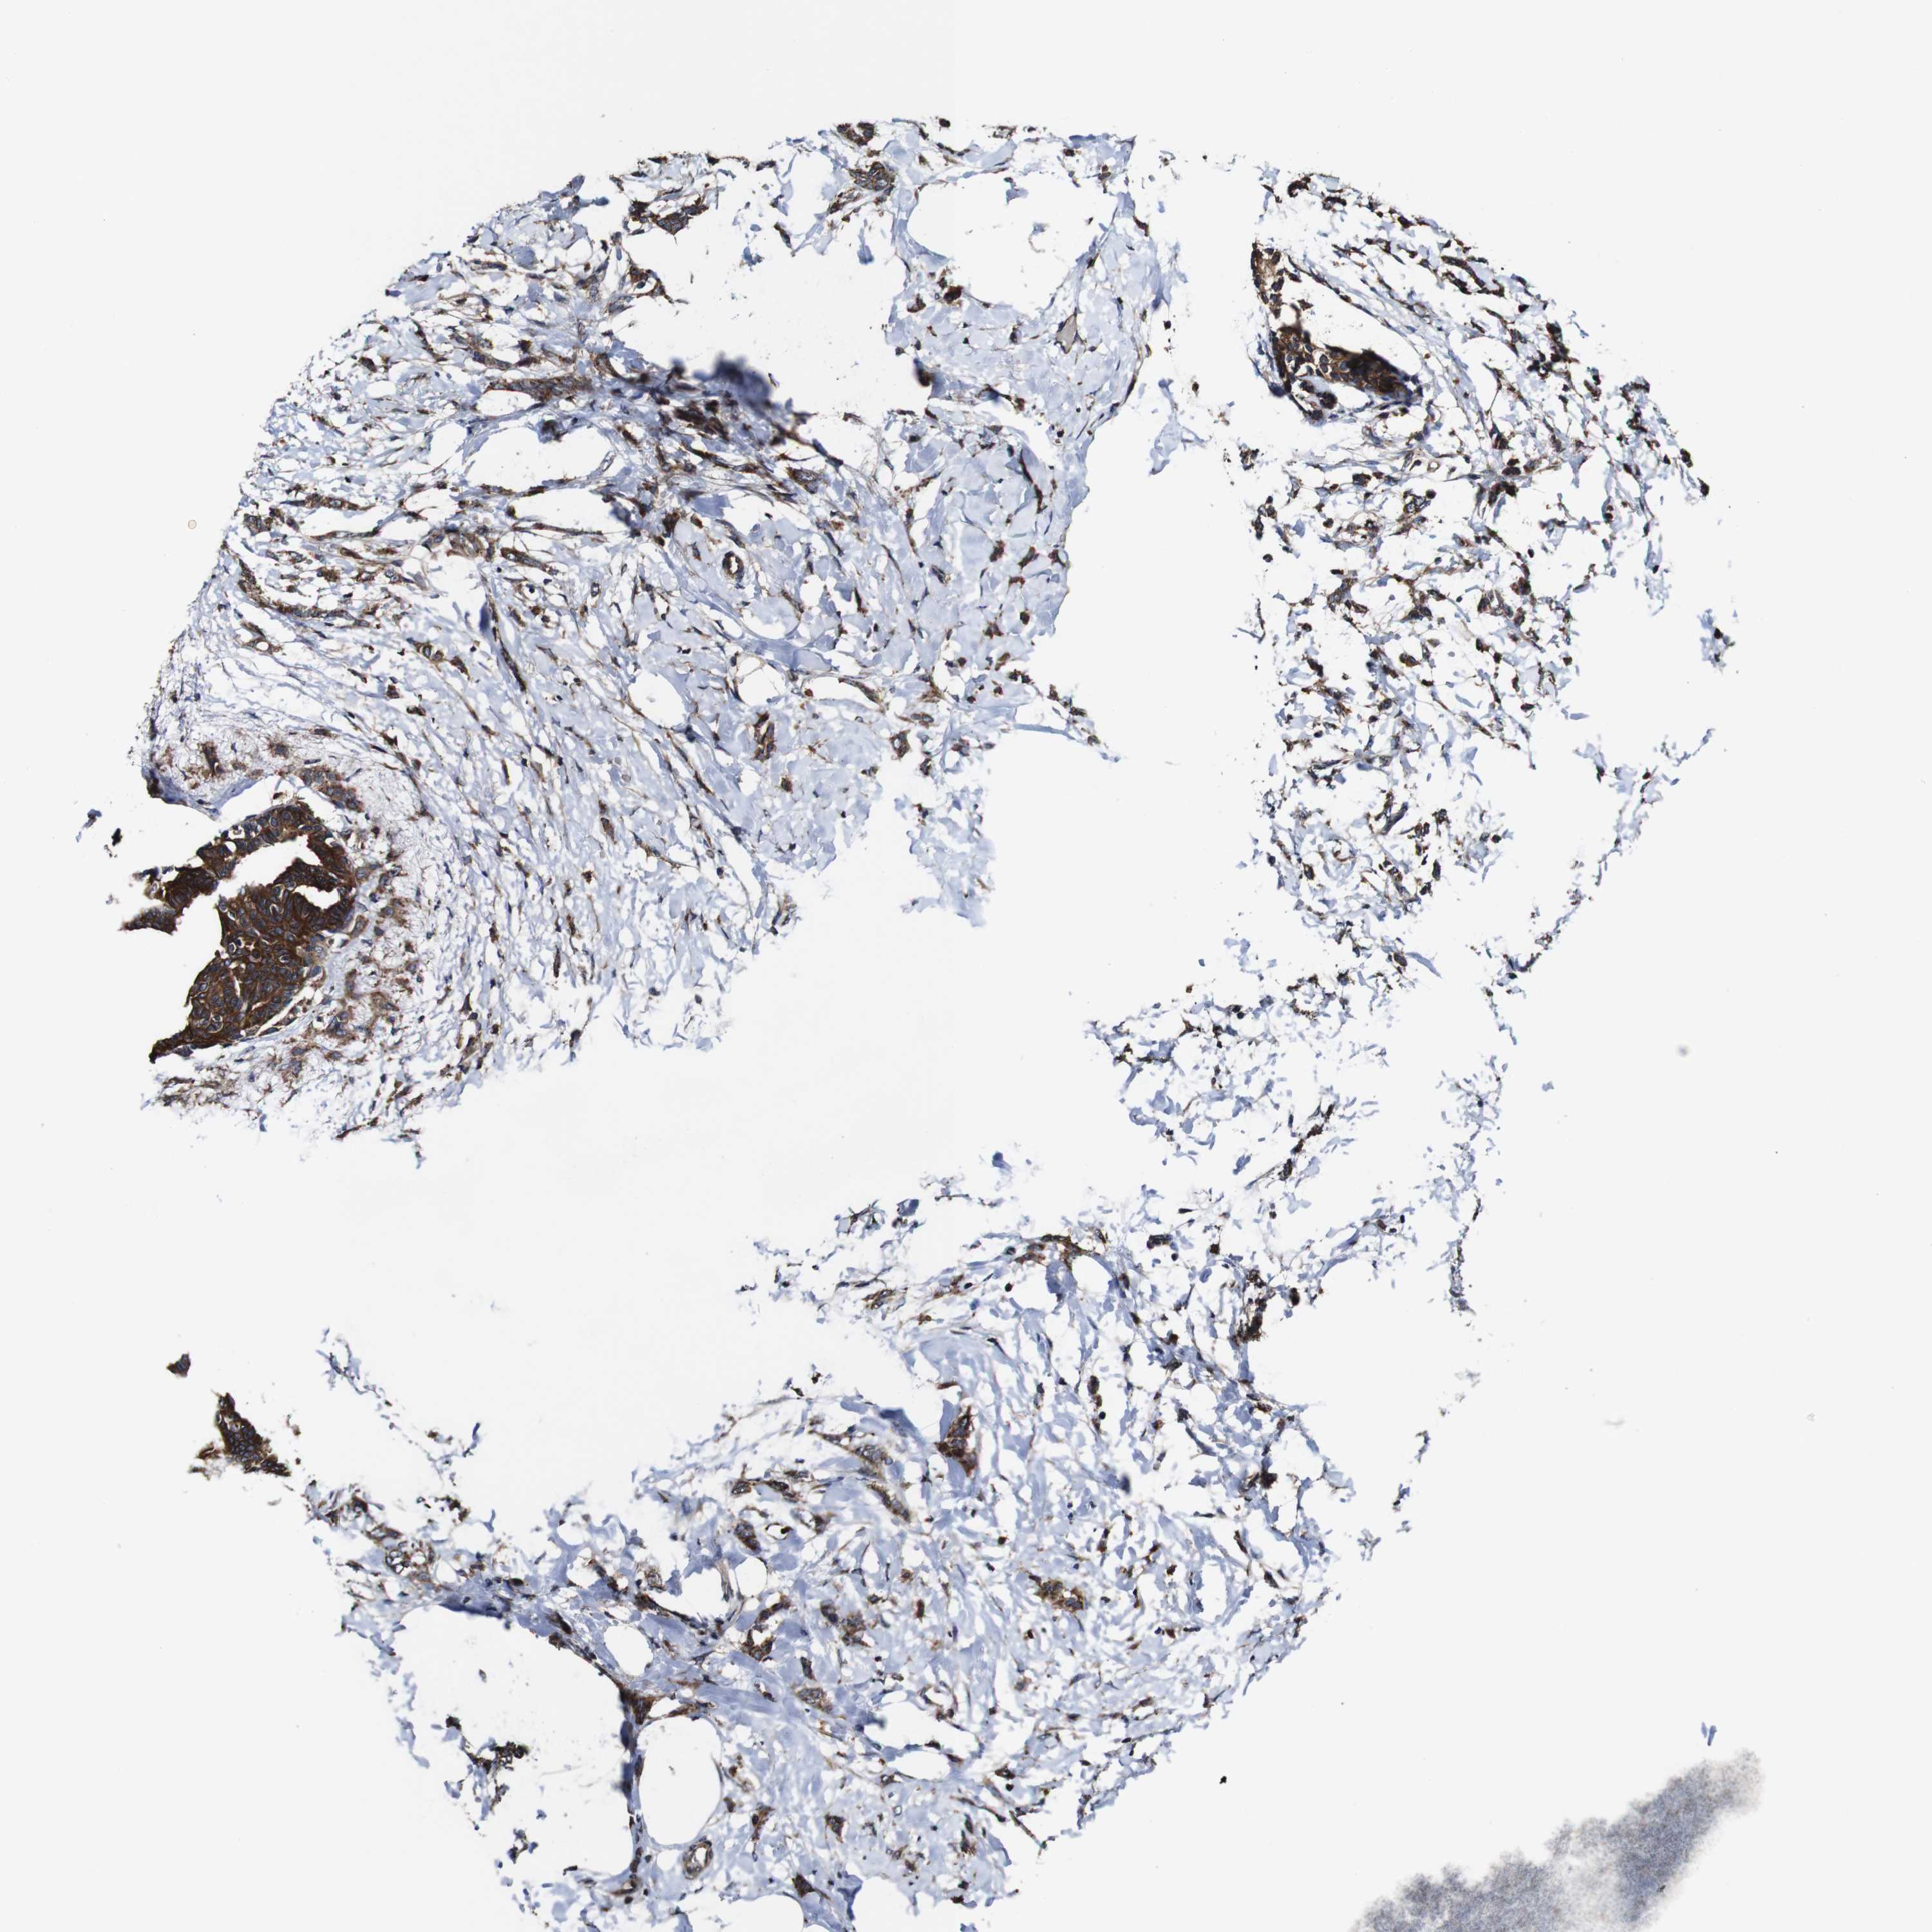

BRCA TCGA BRCA VALIDATION PROTEIN EXPRESSION

Breast cancer

Human cancer